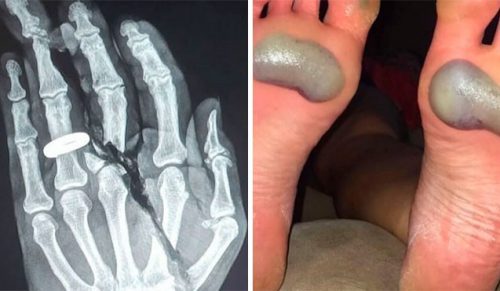

Ostrzeżenie: pamiętaj, że niektóre z tych zdjęć i tematów mogą wydać ci się wyjątkowo niekomfortowe i obrzydliwe.